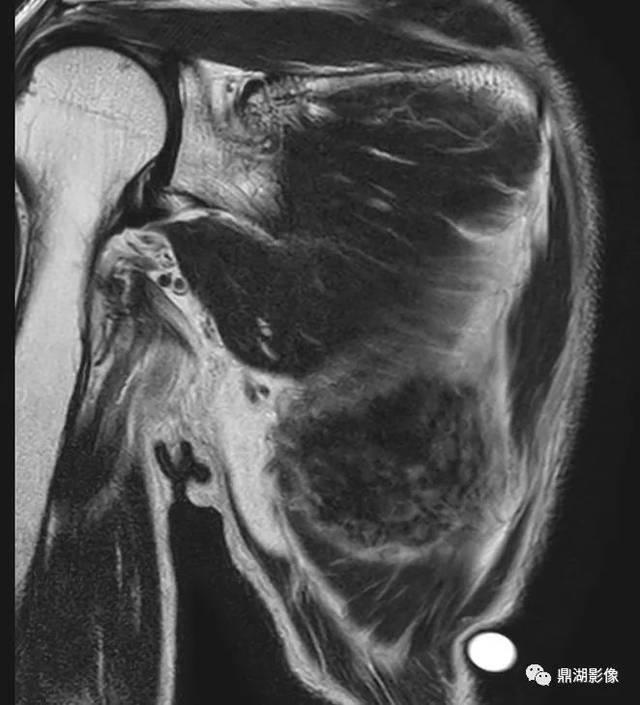

精彩推荐背部弹力纤维瘤超典型影像表现

图片尺寸640x705